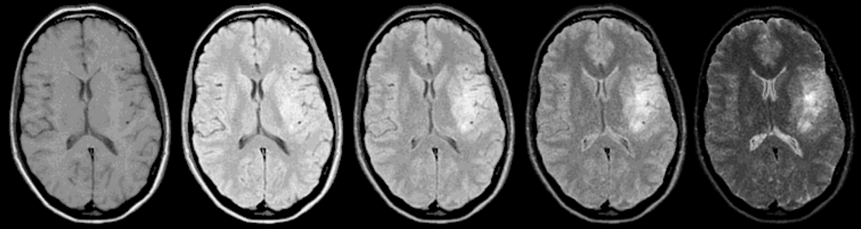

Figure 10-05:

The necessity of image acquisitions with different pulse sequence parameters: Brain, transverse view. SE sequence: TR = 1500 ms; TE from 15 ms to 225 ms. B₀ = 0.5 T.

On the more T2-weighted images, there is a clear­ly visible lesion: an old brain infarction. If you would just perform a T1-weighted study, only very suspicious radiologists will describe possible pa­tho­lo­gi­cal changes: there is a slight mass effect.

Simulation software: MR Image Expert®